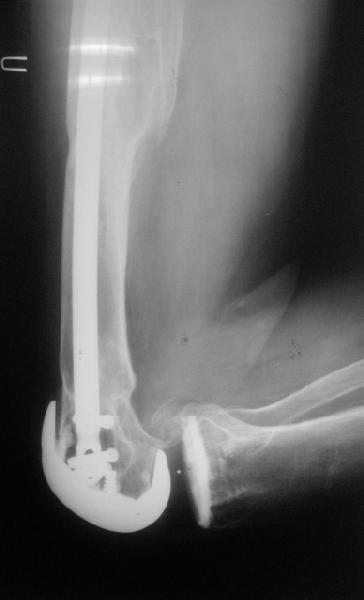

Добрый день! В нашу больничку поступил пациент после бытовой травмы - упал, подвернув ногу. На RG-граммах перелом дистального метаэпифиза бедренной кости. Пациент спутанно рассказывает, где и как он лечился раньше.10 лет назад - коррегирующая остеотомия по поводу деформирующего артроза коленного сустава, 3 года назад в 1 градской больнице г. Москвы выполнено эндопротезирование коленного сустава,площадка большеберцовой кости, со слов пациента, деформировалась около года назад (на фоне остеопороза). Сейчас получил травму в результате падения с высоты собственного роста.Что посоветуете?

Видимо, самое "модное" на сегодня - малоинвазивный остеосинтез пластиной с угловой стабильностью. Распространенный вариант и закрытый интромедуллярный остеосинтез ретроградно. Хотя у нас было бы сделано антеградно - лешево и сердито, действительно малоинвазивно, в сустав не надо влезать. Нет риска прорезания порозной кости с миграцией в сустав, что возможно при ретроградном - гвоздь вводится через вырез в бедреннм компоненте, туда же может и вывалиться. А антеградный - упрется в протез. Как раз вчера заходил больной через полтора года после такой операции. Снимки в приложении.